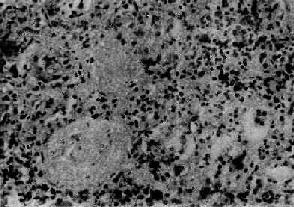

图12-22弥漫性硬化性肾小球肾炎

肾小球纤维化,玻璃样变;肾小管也大部分萎缩纤维化;间质纤维组织增生,有多数慢性炎细胞浸润